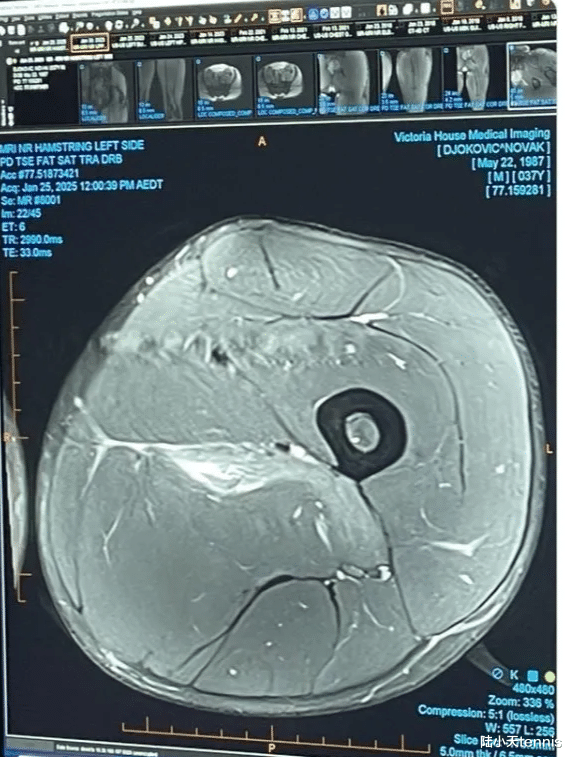

此外,我们再来关注在澳网受伤的德约科维奇,前不久,德约科维奇在个人社交媒体上公布了自己左大腿MRI磁共振扫描检查结果图片,并配文:我想把这个留给所有运动损伤“专家”。

对于德约科维奇目前的伤势,法国网球联合会医生 Vincent Guillard 对此解释说,他在图像上看到了“内收肌的肌肉损伤”,并补充说,在没有整个MRl的情况下,很难从单个切片上看出究竟哪块肌肉受到了影响:“没有看到,很难更精确地判断”。

根据所涉及的肌肉,休息时间可以从三到六周不等,“实际上取决于将要实施的治疗方法”,医生指出。不过,目前根据《福布斯》报道,德约科维奇可能因腿筋撕裂而缺席整整两个月(将缺席印第安维尔斯、迈阿密和蒙特卡洛)。他很有可能会在马德里/罗马甚至直接在罗兰加洛斯复出。